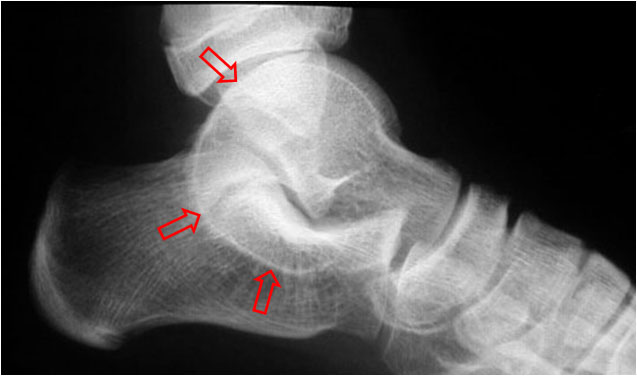

SIGNO DE LA C

Signo de coalición subtalar (fusión calcáneo-astragalina) en la radiografía lateral del tobillo. La «C» se forma por el límite medial de la cúpula talar y el límite posteroinferior del sustentaculum tali.

En la radiografía lateral de tobillo hemos marcado con flechas la «C» que da nombre al signo.